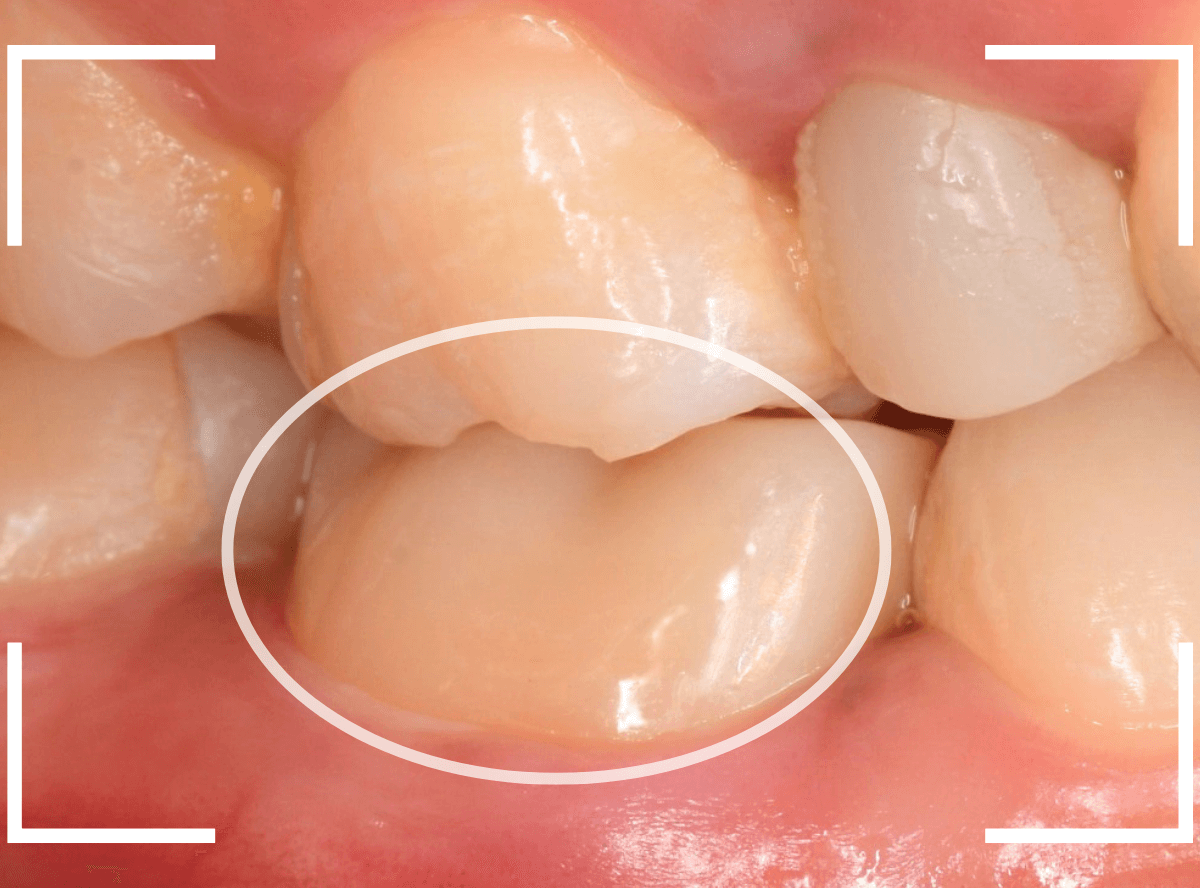

Case.16 保険のさし歯(レジン前装冠)をジルコニア・セラミックへ

以前に治療した上のさし歯を綺麗にやり直したいというご相談の患者さんです。

保険診療で行うさし歯「レジン前装冠」が入っています。

「レジン前装冠」は裏から撮影した写真を見ていただければわかるように、銀歯の上にレジン(プラスチック)を盛ったさし歯で、実質的には銀歯です。

銀歯の上にプラスチックを盛るために、歯をかなり大きく削る必要があったり、短期間で劣化・変色する(この方の差し歯も劣化してのっぺりした黄土色になっています)、金属の色素が歯肉に溶け出して歯肉が黒くなる(メタル・タトゥー)などのデメリットがあります。